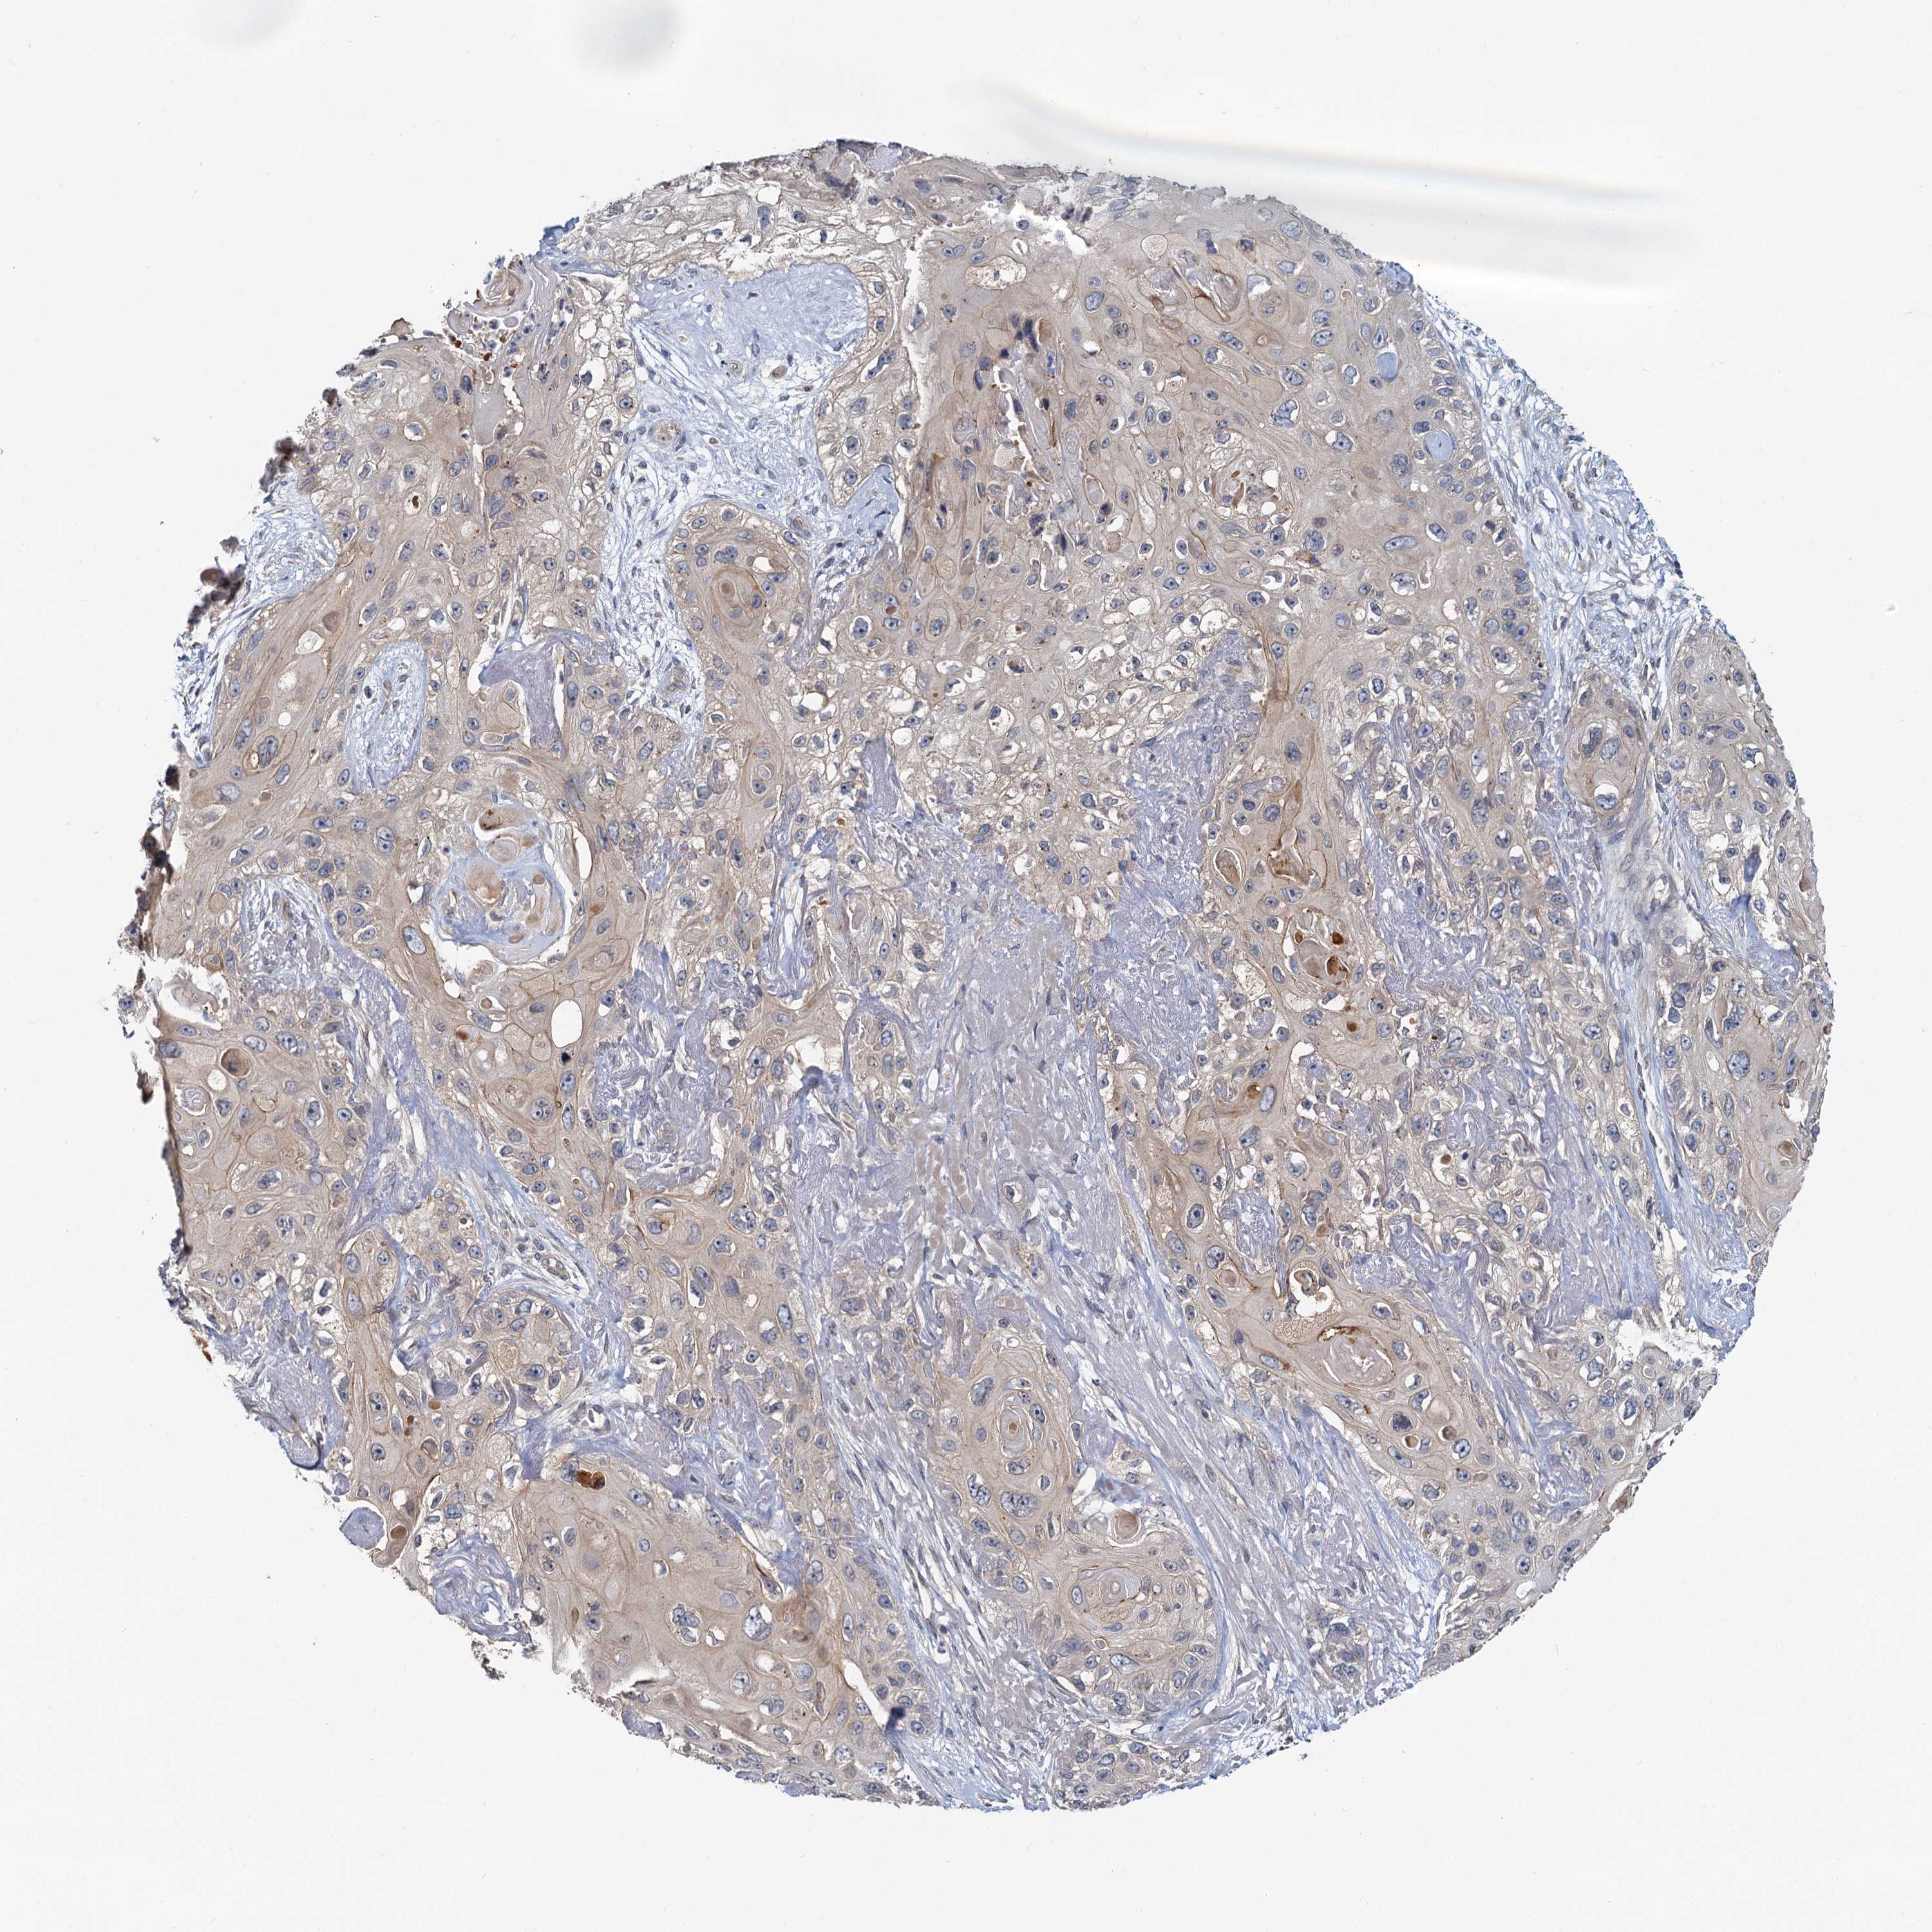

SKIN CANCER - Protein expressioni

A mouse-over function shows sample information and annotation data. Click on an image to view it in a full screen mode. Samples can be filtered based on level of antibody staining by selecting one or several of the following categories: high, medium, low and not detected. The assay and annotation is described here.

Antibody staining in the annotated cell types in the current human tissue is reported as not detected, low, medium, or high, based on conventional immunohistochemistry profiling in selected tissues. This score is based on the combination of the staining intensity and fraction of stained cells.

Each image is clickable and will lead to virtual microscopy that enables deeper exploration of all samples and also displays staining intensity scores, fraction scores and subcellular localization as well as patient and tissue information for each sample.

Antibody HPA039774

Staining

High

Medium

Low

Not detected

Intensity

Strong

Moderate

Weak

Negative

Quantity

>75%

75%-25%

<25%

None

Location

Nuclear

Cytoplasmic/membranous

Cytoplasmic/membranous,nuclear

Basal cell carcinoma

Squamous cell carcinoma, NOS

Squamous cell carcinoma, metastatic, NOS